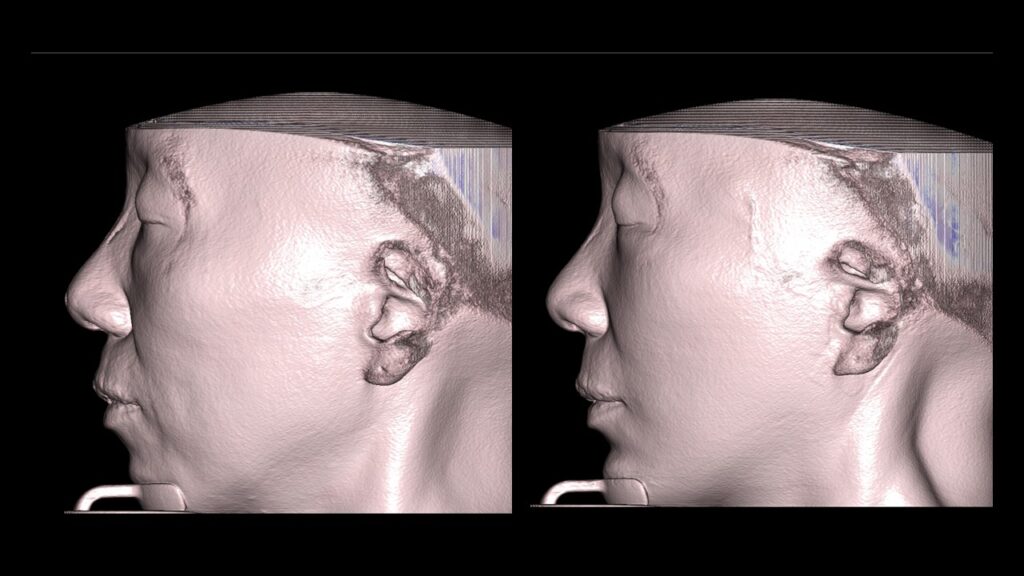

4. Case Studies (3DCT & Medical Photos)

-

Case 1: (Zygoma Reduction + Face Lift) 1-year post-op shows a significant reduction in mid-face width and improvement in nasolabial folds.

-

Case 2: (Zygoma + Chin Advancement + Face Lift + Brow Lift) Dramatic improvement in the side profile and double chin within just 1 month.